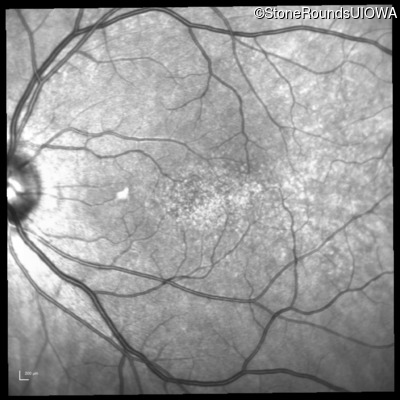

Infrared Fundus Photograph - Right - 20/20 +1 sc

Exemplar